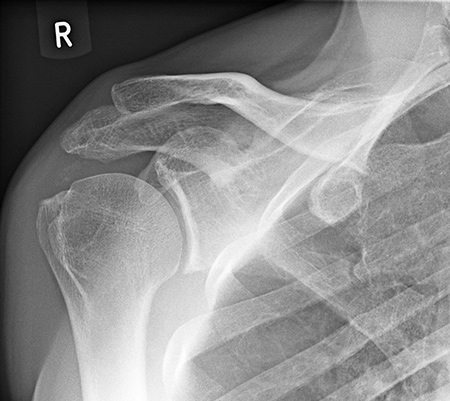

Abb. 2: Kalkschulter nach auswärtiger neunmaliger radialer Druckwelle

Abb.3: gleicher Patient nach viermaliger hochenergetischer ESWT